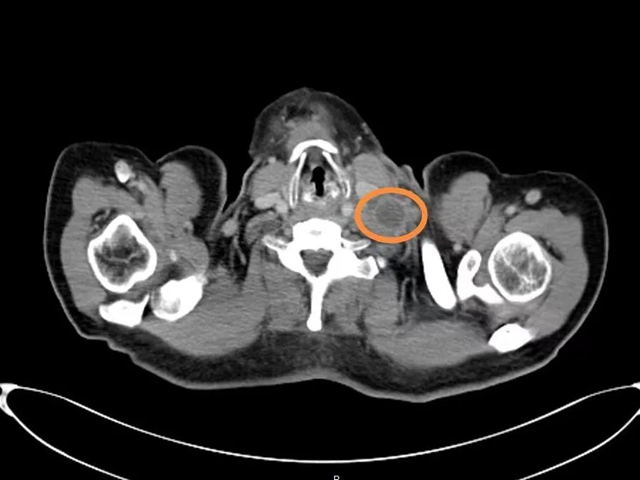

入院后,通过颅脑+颈部+胸部+全腹部增强CT检查,结果提示:左侧颈根部软组织肿块,最大截面大小约为3.4cm*3.3cm,后下纵隔、肝胃间隙、胃贲门周围软组织结节及肿块、部分融合,纵隔、腹膜后、盆腔左侧淋巴结肿大,脾内、双肺多个小结节。结合严大爷病史,考虑为淋巴瘤伴转移可能性较大。

2周期化疗后,复查CT左侧颈根部软组织肿块,最大截面大小约为2.4cm*2.2cm。与上次检查结果比较,颈、胸、腹部淋巴结均有缩小,左侧胸腔积液减少,双肺结节有明显缩小,部分已被吸收。

治疗前